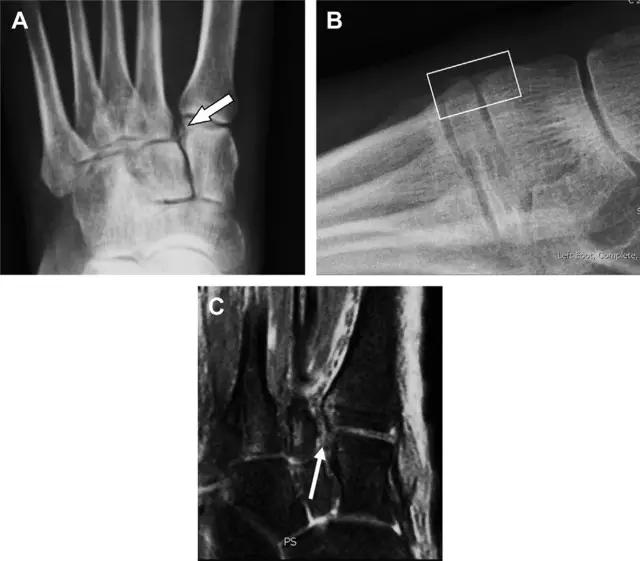

与跗跖关节韧带相关的骨折常由旋前或旋后的跖屈损伤引起。尽管跗跖关节骨折脱位仅占所有骨折的 0.2%,但是约 20% 的这些骨折在初次检查时被漏诊。初次 X 片可能示正常,但是负重位 X 线片常常提示脱位或半脱位。

典型表现:第二跖骨底和内侧楔骨之间的骨折碎片,跖骨间间隙增宽(图 8)。脱位亦可发生在舟骨-内侧楔骨关节,导致另一种变异的跗跖关节损伤(图 9A)。此外,骰骨的小块皮质撕脱在足部斜位片上可清晰显示(图 9B)。

图 8 从马上摔落的患者,跗跖关节骨折。A 正位片示内侧楔骨旁边的小骨折碎片(箭头),第二跖骨底向外半脱位;B 负重位侧位片示第二跖骨相对中间楔骨向背侧轻微移位(长方形);C STIR 序列 MRI 图像示跗跖关节韧带断裂(箭头),第一至第三跖骨、内侧楔骨及中间楔骨均骨髓水肿

图 9 变异的跗跖关节骨折。A 另一种类型的跗跖关节损伤,中间楔骨向内侧半脱位(弧形箭头),从而使第一、第二跖骨间间隙变宽,需注意,骨折在靠近内侧楔骨处(箭头);B 外侧跗跖关节损伤伴随从骰骨跖骨韧带的骰骨撕脱(箭头),需注意,第五跖骨底近端处存在软策划水肿(空箭头)